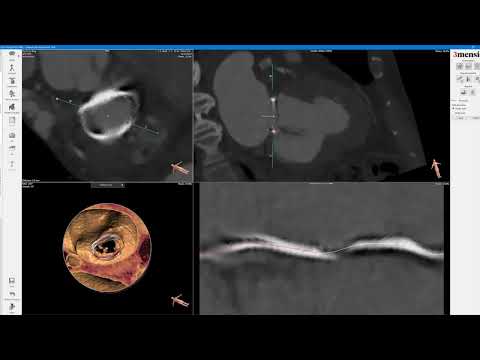

3Mensio CT Pre-case Planning: Mitral Valve-in-Valve TMVR in Magna Valve

3Mensio CT Pre-Case Planning: Mitral Valve-in-Ring (MVIR) TMVR

TMVR in Mitral Stenosis – Advanced pre-procedural planning aided by 3D - PCR Valves e-Course 2020